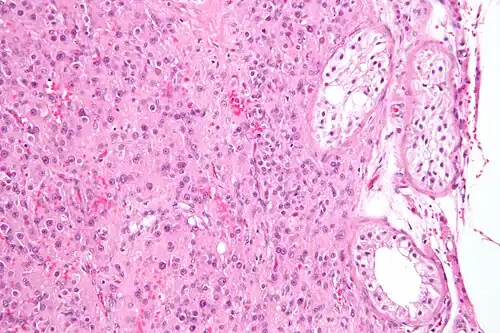

| Micrograph of a granulosa cell tumour, a type of sex-cord–gonadal stromal tumour. H&E stain. | |

Definitive diagnosis of these tumours is based on the histology of tissue obtained in a biopsy or surgical resection. In a retrospective study of 72 cases in children and adolescents, the histology was important to prognosis.[8]

A number of molecules have been proposed as markers for this group of tumours. CD56 may be useful for distinguishing sex cord–stromal tumours from some other types of tumours, although it does not distinguish them from neuroendocrine tumours.[9] Calretinin has also been suggested as a marker.[10] For diagnosis of granulosa cell tumour, inhibin is under investigation. Granulosa cell tumours and Sertoli-Leydig cell tumours have specific genetic mutations that are characteristic and can help support the diagnosis.[1]